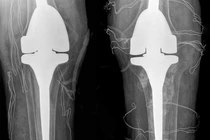

Anh H.T (37 tuổi, trú tại Hà Nội) đến bệnh viện khám trong tình trạng hai khớp gối co cứng, khó đi lại. Anh T. bị bệnh gout, gần đây thường xuyên uống thuốc được người thân mua từ nước ngoài về kèm quảng cáo chữa bệnh gout với thành phần “hoàn toàn thảo mộc”.

Mỗi đợt gout cấp, anh uống “thuốc” này giảm đau nên lên mạng mua thêm và dùng thường xuyên. Gần đây, bệnh gout của bệnh nhân nặng hơn, xuất hiện các hạt tophi lớn khắp cơ thể, hai khớp gối co cứng, khó đi lại.